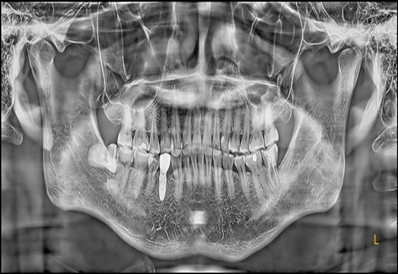

November 23, 2025: Implant follow-up examination. The implant surgical site showed excellent healing, with no abnormal bone density around the implant and satisfactory osteogenesis. The third-stage impression taking was implemented. The panoramic radiograph below confirmed the complete seating of the implant impression coping.

December 4, 2025: Definitive crown delivery. The margin of the implant-supported crown exhibited optimal adaptation.